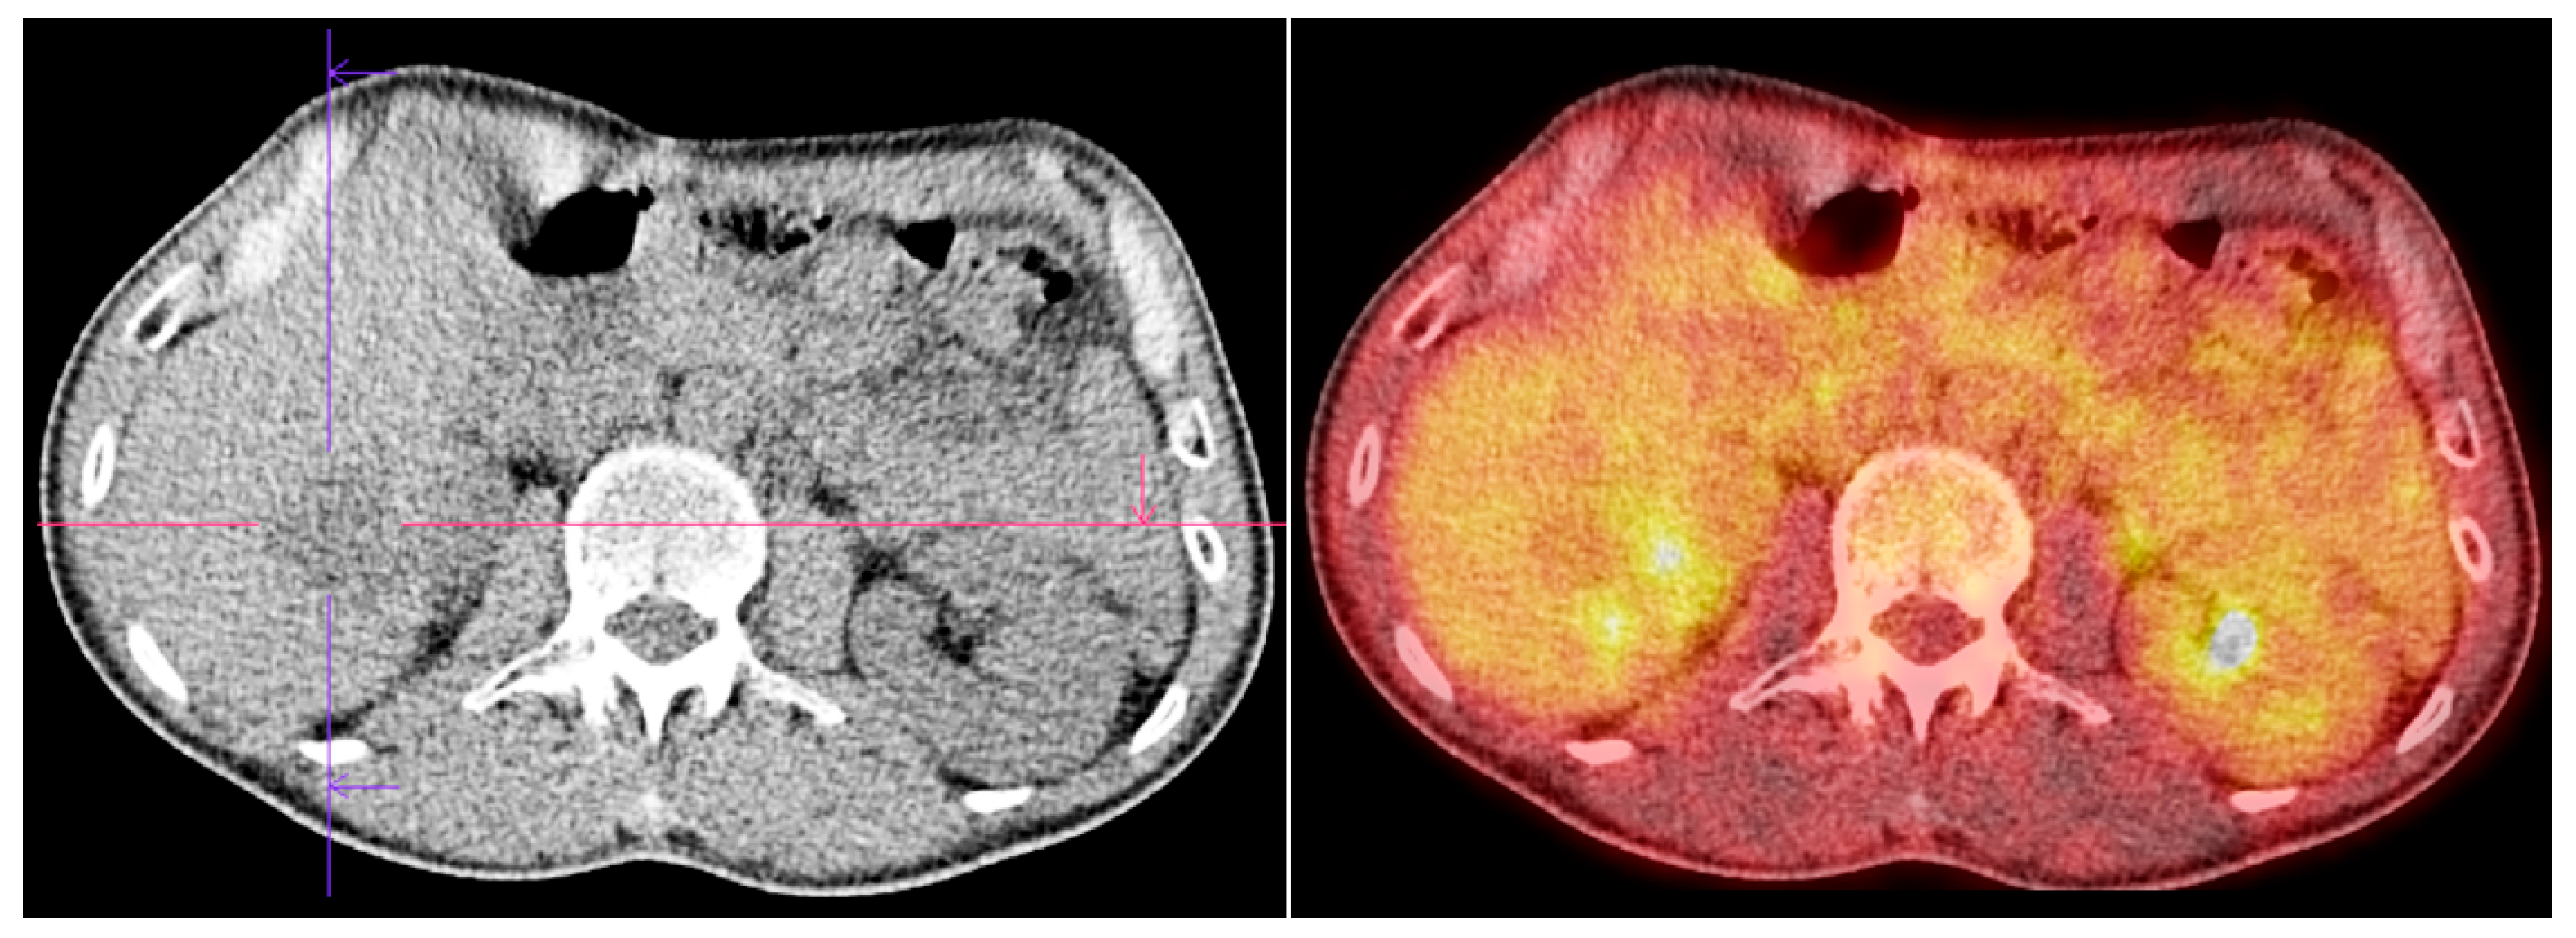

Sabljak, P.; Djuric-Stefanovic, A.; Bubanja, M.; Odalovic, S.; Ivanovic, N.; Mitrovic-Jovanovic, M.; Skrobic, O. High-Risk Esophageal GIST: Imaging and Therapeutic Impact on Atypical Metastatic Lesions. Diagnostics 2025, 15, 1802. https://doi.org/10.3390/diagnostics15141802